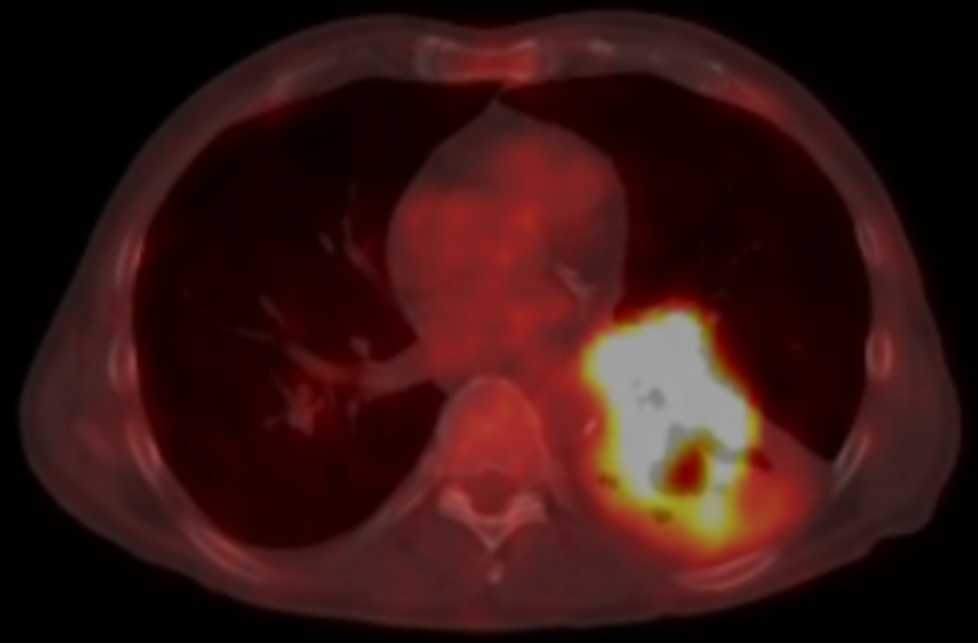

| large left lung tumour involving the left main bronchus |